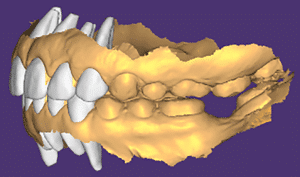

Mme AB vient en consultation pour deux raisons. La première est une douleur intense à chaque fois qu’elle boit ou mange froid. La deuxième est l’apparence de son sourire. Elle trouve que ses dents ont « raccourci » et qu’elles « s’effritent ». C’est devenu un complexe handicapant. À L’examen clinique on observe (Fig.1a, b, c, d, e) une usure vestibulaire de toutes les dents : plus prononcée au maxillaire et assez légère sur les incisives mandibulaires, une classe III canine et molaire droite, une classe I canine et molaire gauche avec une légère déviation des milieux et une usure importante des faces palatines du bloc IC maxillaire ainsi que des faces occlusales de 16 et 26. On constate aussi que les faces occlusales des autres dents sont moins touchées en apparence. On observe que les amalgames de 36 et 48 sont en relief par rapport à la dent support. Il est raisonnable de supposer qu’à l’origine ils devaient obturer une cavité et donc être à l’intérieur de la dent. Ceci témoigne donc aussi d’une forte usure sur 36 et 46. On observe enfin que les courbes de Spee sont complètement plates.

Fig.1a, b, c, d, e : Examen clinique.

Fig.1b.

Fig.1c.

Fig.1d.

Fig.1e.